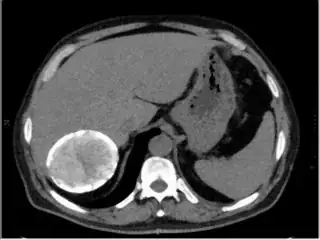

Here is other sample image with rgb range varying from 110 to 180 sample image 3.

Please help.